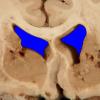

Subcortical Arteriosclerotic Encephalopathy (5)